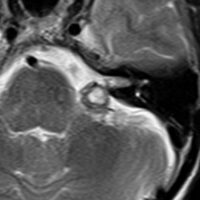

脳幹部の海綿状血管腫を手術するとき

左上のT2*でみられるように多発性海綿状血管腫の成人男性に発生した中脳海綿状血管腫です。複視と歩行失調で発症して,数回の脳幹部出血を繰り返し,水頭症になったために第3脳室開窓術がなされました。それでも出血は止まらず、両側の動眼神経麻痺による両側眼瞼下垂,歩行失調,嚥下障害などさまざまな中脳症状が進行しました。

しかたがないので手術で摘出しました。なんとか眼瞼が持ち上がるようになり歩行も可能で嚥下もできます。幸いだったのは感覚路(脊髄視床路)の障害による体性疼痛が生じなかったことです。

手術は経テント法 OTA という手法でした(クリックと手技が書いてあります)

片方の下丘の損傷だけでは神経脱落症状が出ないので,中脳内部の腫瘍を摘出するには下丘という狭い場所を切開して入りますが,この患者さんは左上丘も出血のために破壊されていて,間口が広かったといえます。でもこの手術は難しすぎるので決して積極的にはしません。